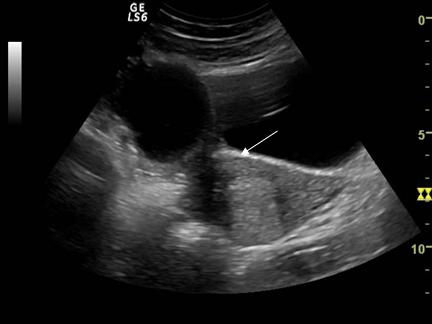

Fig. nr.387. Formatiune anecogena uniloculara cu perete subtire ( sageata ), fara lichid in Douglas ( chist functional , la o pacienta de 15 ani , la ecografia abdominala